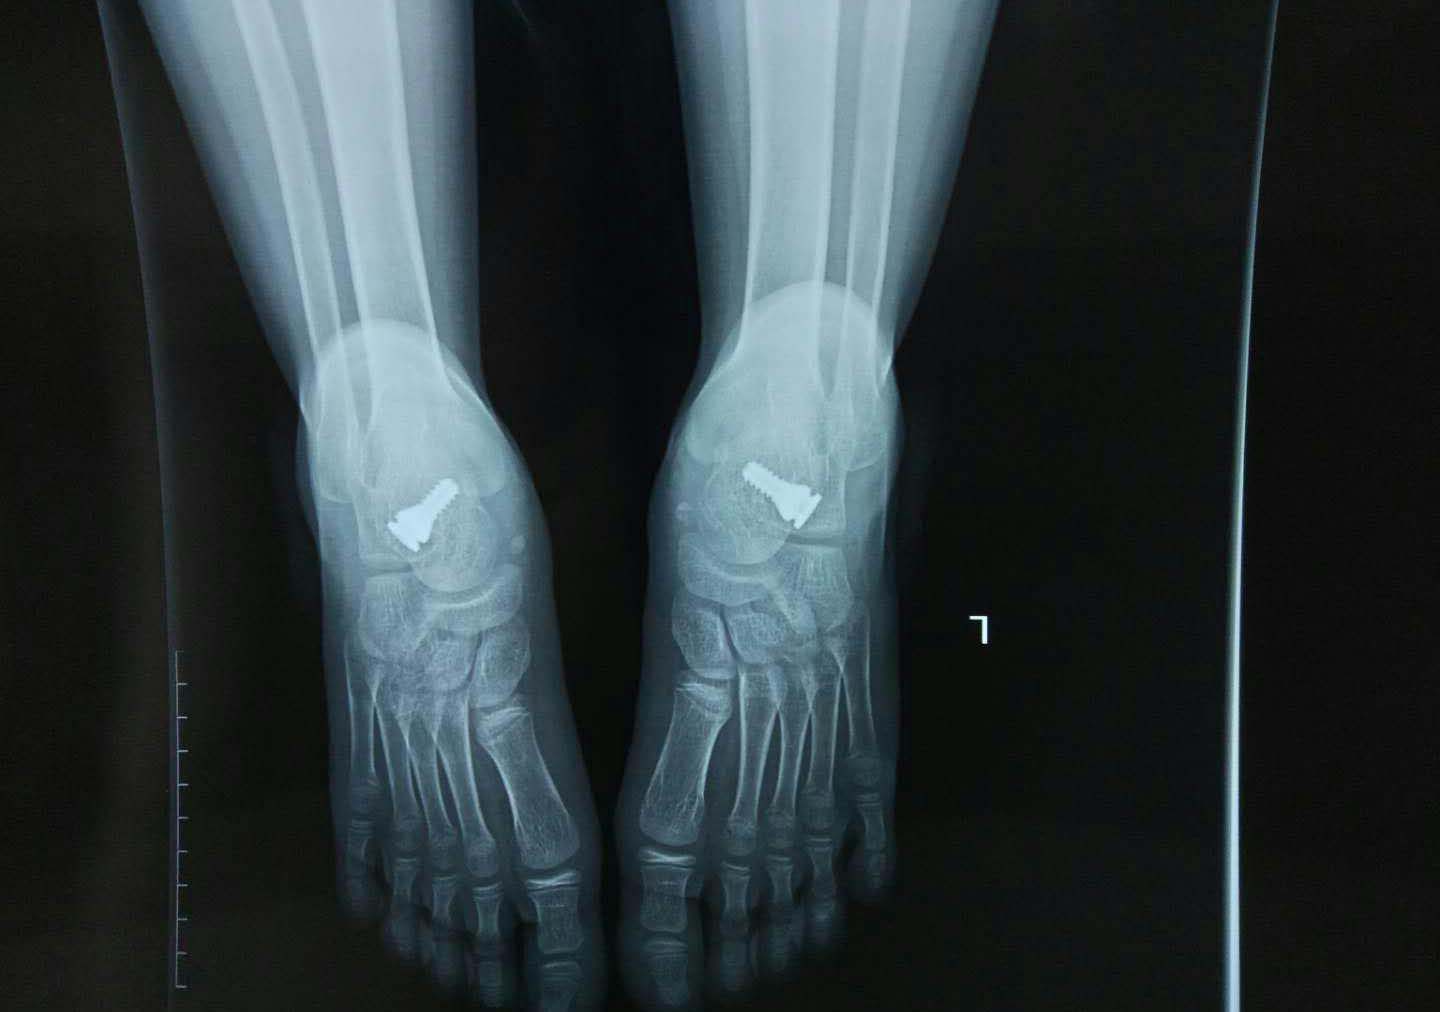

治疗二、微创手术,放置距下关节稳定器,适合于6岁以上儿童,成人也可以使用。

距下关节稳定器虽然贵,却是治疗平足症的终极武器!